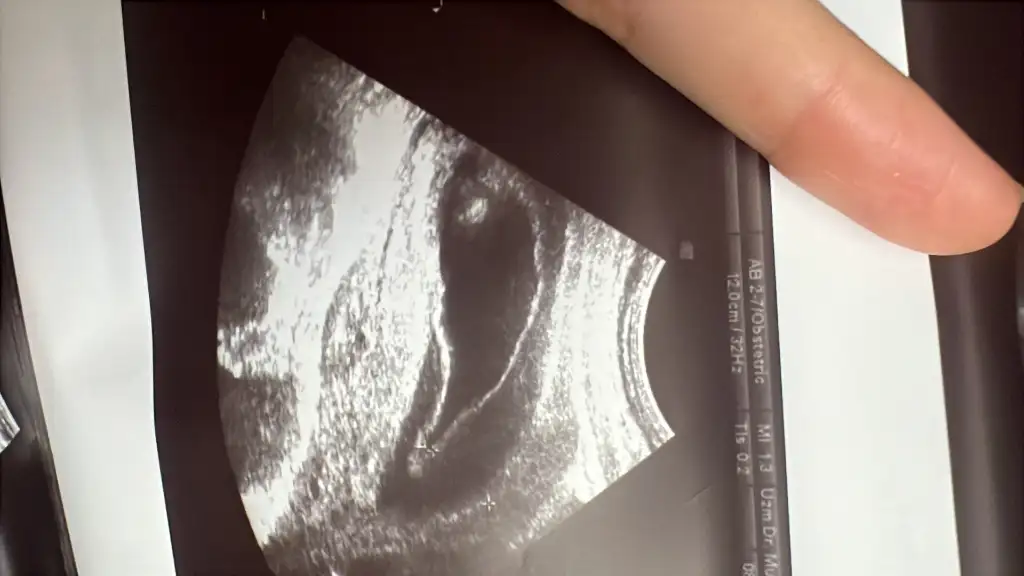

Aynı durumdayız senınle benımde 14.haftam. Ne yazıkki böyle kanamalar olabılıyor gebelikte. Kanama alanı zamanla küçülüyor. Çok arastırdım çok kişiyle konuştum. Herseyden onemlisi stres yapıp daha çok tetıklememek. Cok zor biliyorum. 1 aydır aynı durumu yasıyorum ama bi şekilde baş etmemiz gerekiyor. Yatın dinlenin kendinizi cok dinlemeyin. Stresiniz azalsın once sonra inşallah tutanacaktır bebişinYaşadığım şehirde maalesef imkanım kısıtlı tekrar büyümesi daha da büyüyüp beneğe zarar verir diye en büyük korkum şuan

Senin kaç cm. Rabbim sağlıkla kucağımıza almayı nasip eder inşallahAynı durumdayız senınle benımde 14.haftam. Ne yazıkki böyle kanamalar olabılıyor gebelikte. Kanama alanı zamanla küçülüyor. Çok arastırdım çok kişiyle konuştum. Herseyden onemlisi stres yapıp daha çok tetıklememek. Cok zor biliyorum. 1 aydır aynı durumu yasıyorum ama bi şekilde baş etmemiz gerekiyor. Yatın dinlenin kendinizi cok dinlemeyin. Stresiniz azalsın once sonra inşallah tutanacaktır bebişin

6 cmdi benımde. Carsamba gidicem tekrar bekliyorum bendeSenin kaç cm. Rabbim sağlıkla kucağımıza almayı nasip eder inşallah

Şuan tamamen gitti miBenim de 10 haftalıkkem başıma geldi 6.5 cmlik kanama alanım vardı bebek 4.5 cm di şu an 18. Haftayım ilk başlarda kırmızı sonra kahverengi devam etti uzun bir süre. Bol bol su için dinlenin ve ayağa sadece tuvalet için kalkın.